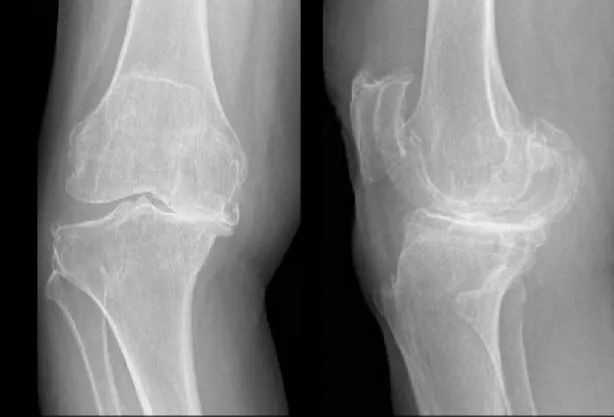

一般来说,膝骨关节炎的X线表现为:骨质增生、关节间隙狭窄不对称、软骨磨损、关节游离体、半月板钙化、髌骨软化等。